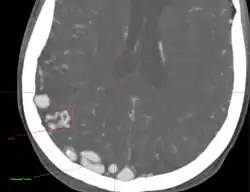

- Originally described by Luschka and Virchow in the mid-1800s, AVMs are abnormal communications between arteries and veins without the normal capillary flow.

- Abnormal communication between artery and vein, with disproportionate and unbalanced hydrodynamic stress across them. The direct connection between the arterial and venous systems exposes the venous system to abnormally high pressures and results in the formation of enlarged feeding vessels and enlarged draining venous structures.

- Point of abnormal communication is known as the nidus